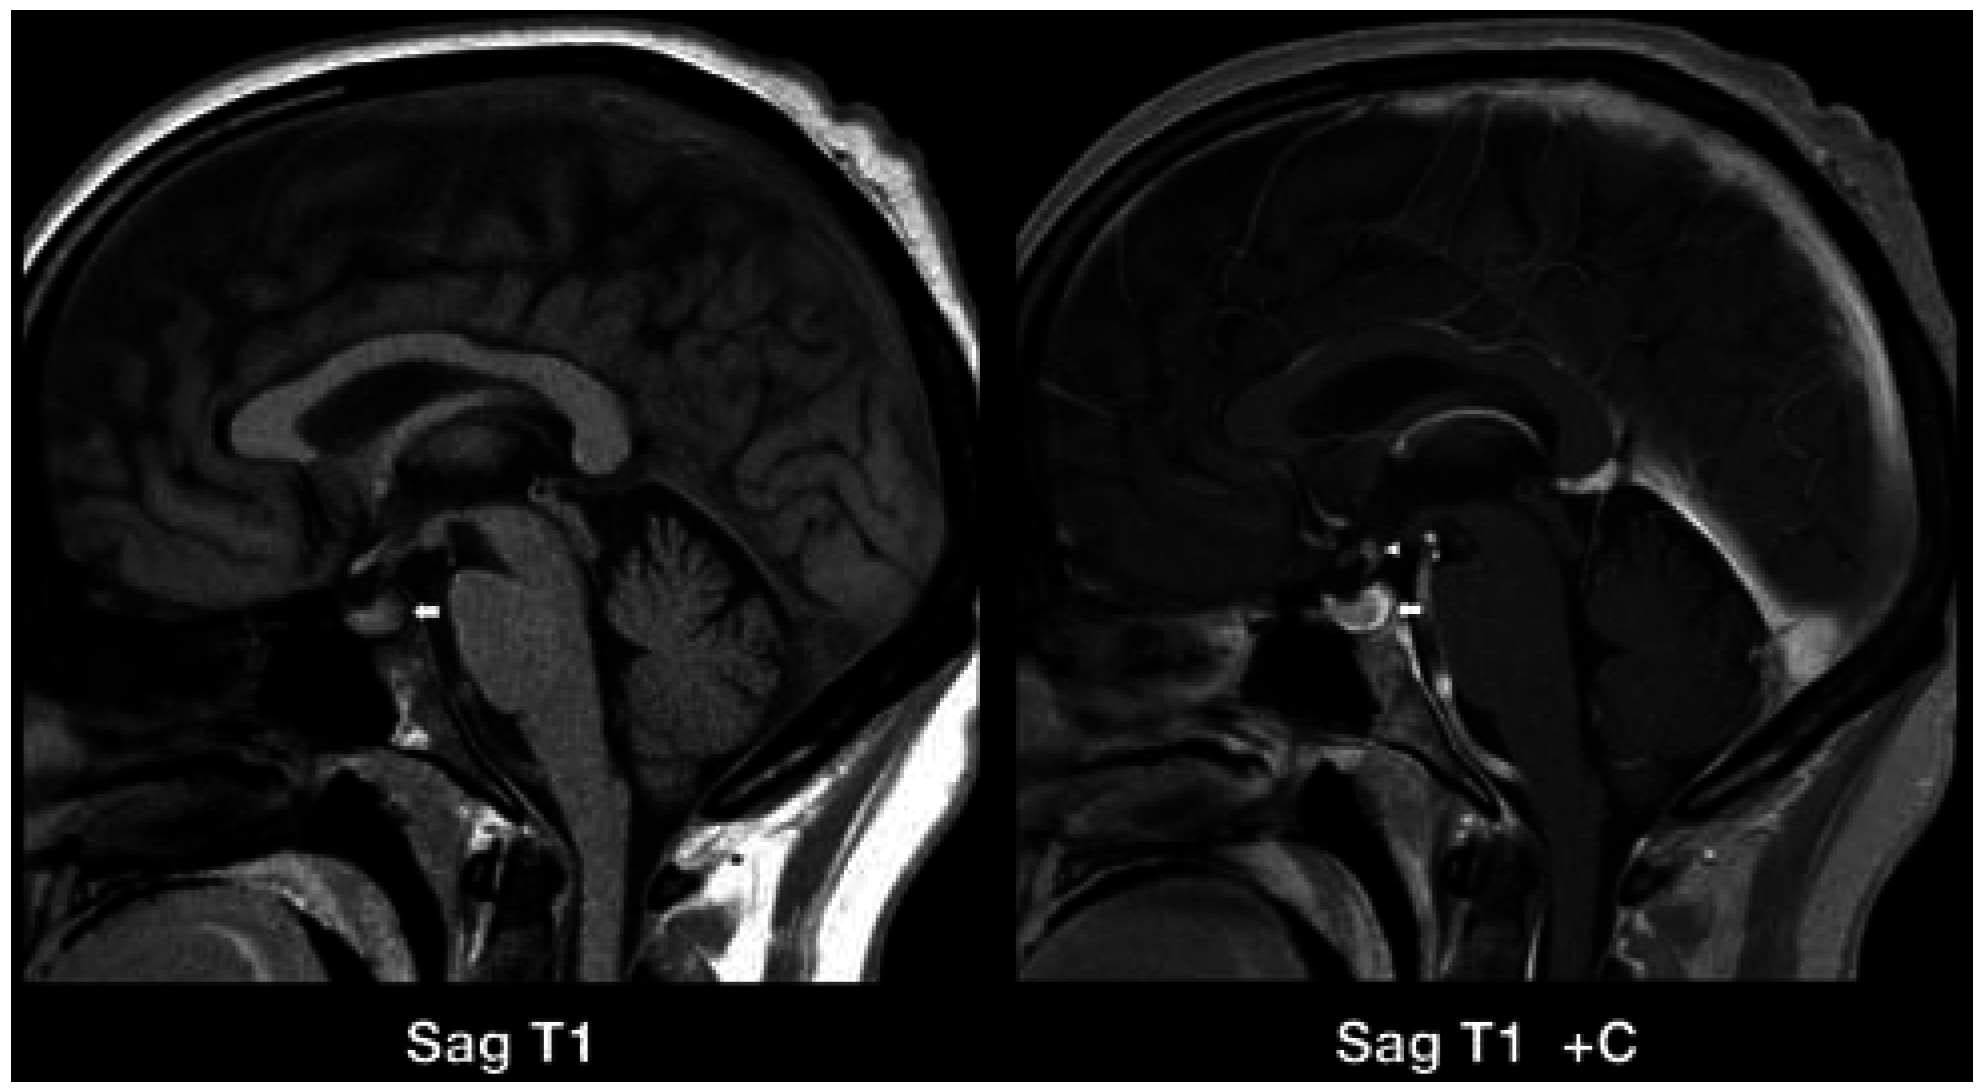

4. Authors’ Institution Case Reports